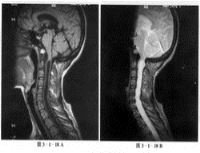

小脑扁桃体下疝畸形